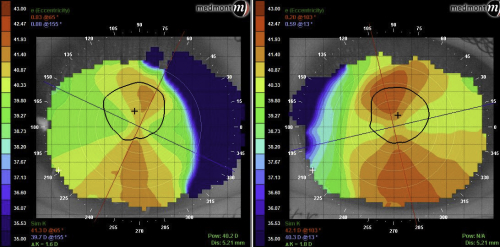

Unfortunately, not all post-LASIK refractive error is regular. Post-LASIK ectasia can be highly debilitating and severely limit the corrective options available. In some cases, highly customised orthoK lenses can be used to remodel the irregularity and improve vision. A patient of mine in his mid-50’s had myopic LASIK done over a decade before but had developed severe post-LASIK ectasia in his right eye and moderate ectasia in his left eye since then. The better left eye had a variation of 7D of axial power along the 150 meridian leading to unaided acuity of 6/12 and a refraction of -1.00DS (6/6 with aberrations). This gentleman was very keen to explore his orthoK options and we settled on fitting only the left eye with a custom myopic ortho-K lens. This had an aspheric back optic zone with a diameter to match the treatment zone of his myopic LASIK.

Our second patient’s EyeSpace simulation of his customised myopic orthoK lens over his irregular post-LASIK left cornea

In these cases, interpreting the axial difference map can require some thought. Rather than creating a uniform degree of refractive change in the form of a ‘bulls-eye’ that we are used to with simple myopic orthoK, instead we are trying to create a post-orthoK cornea that is more regular. This will decrease the aberrations in the optical system. You will see in the axial difference map that the orthoK lens has succeeded in steepening the flat section of the cornea at axis 150, and flattening the steep section opposite this. The patient was seeing 6/6 unaided with only a quarter diopter of residual cylinder when using his lens. He commented that the halos around streetlights were much reduced, although not completely eliminated. His main gripe was that we couldn’t do the same treatment on his severely ectatic right cornea due to its ‘munted’ irregularity! Patients with other forms of irregular corneae such as forme fruste keratoconus can also be treated with orthoK lens in a similar way (often with an inferior ‘tuck’ quadrant specific design) as long as the practitioner is mindful to monitor the cornea at each aftercare for signs of progression or insult.

Axial difference maps showing our second patient’s irregular post-LASIK corneal topography in Exam A, the more regular post-orthoK cornea in exam B and the unusual difference map showing how this patient’s cornea has been modified to decrease the aberrations due to his ectasia